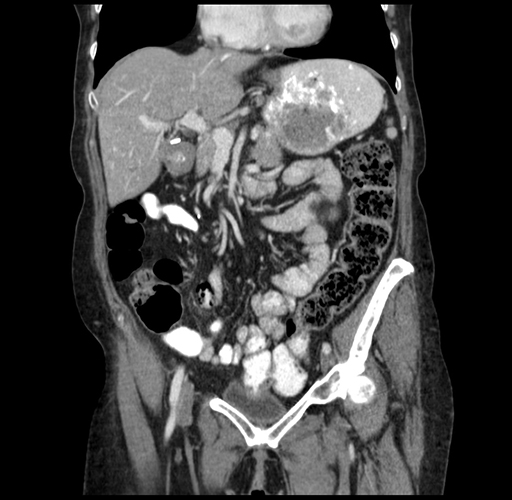

Pre-Chemo: Coronal Venous

Coronal Venous